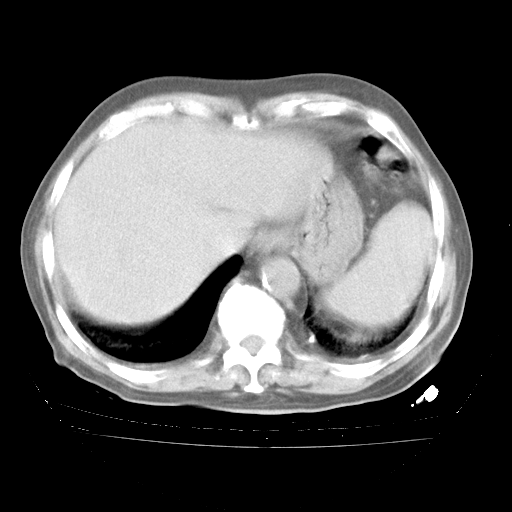

4月28日肺部CT

个人阅读4.14日肺部CT平扫:纵隔窗无异常,但肺窗示:双下肺内、后基底段有片絮状侵润影,部位以后基底段为著,以间质改变为主,呈急性肺泡炎征像,和首次住院影像学有相似之处。仅是个人读片,明日请相关专家再读片哈。其它建议同上。